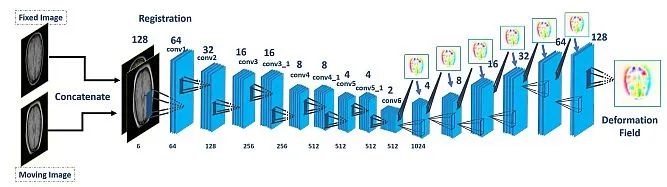

基于深度学习的配准: 它应用卷积神经网络(CNNs)直接从图像对学习变换。它可以处理复杂的变换和大数据集,但需要额外的训练数据。此外,在训练期间计算成本较高。

医学图像配准旨在找到最佳的空间变换,以最佳地对齐现有的解剖结构。它被广泛应用于许多临床应用中,例如图像重建、图像引导、运动跟踪、分割、剂量积累等。医学图像配准是一个宽泛的主题,可以从不同的角度来考虑。

从输入图像的角度来看,配准方法可以分为单模态、多模态、跨患者和同患者配准。从变形模型的角度来看,配准方法可以分为刚性、仿射和可变形方法。从感兴趣区域(ROI)的角度来看,配准方法可以根据解剖部位分组,例如大脑、肺部配准等。